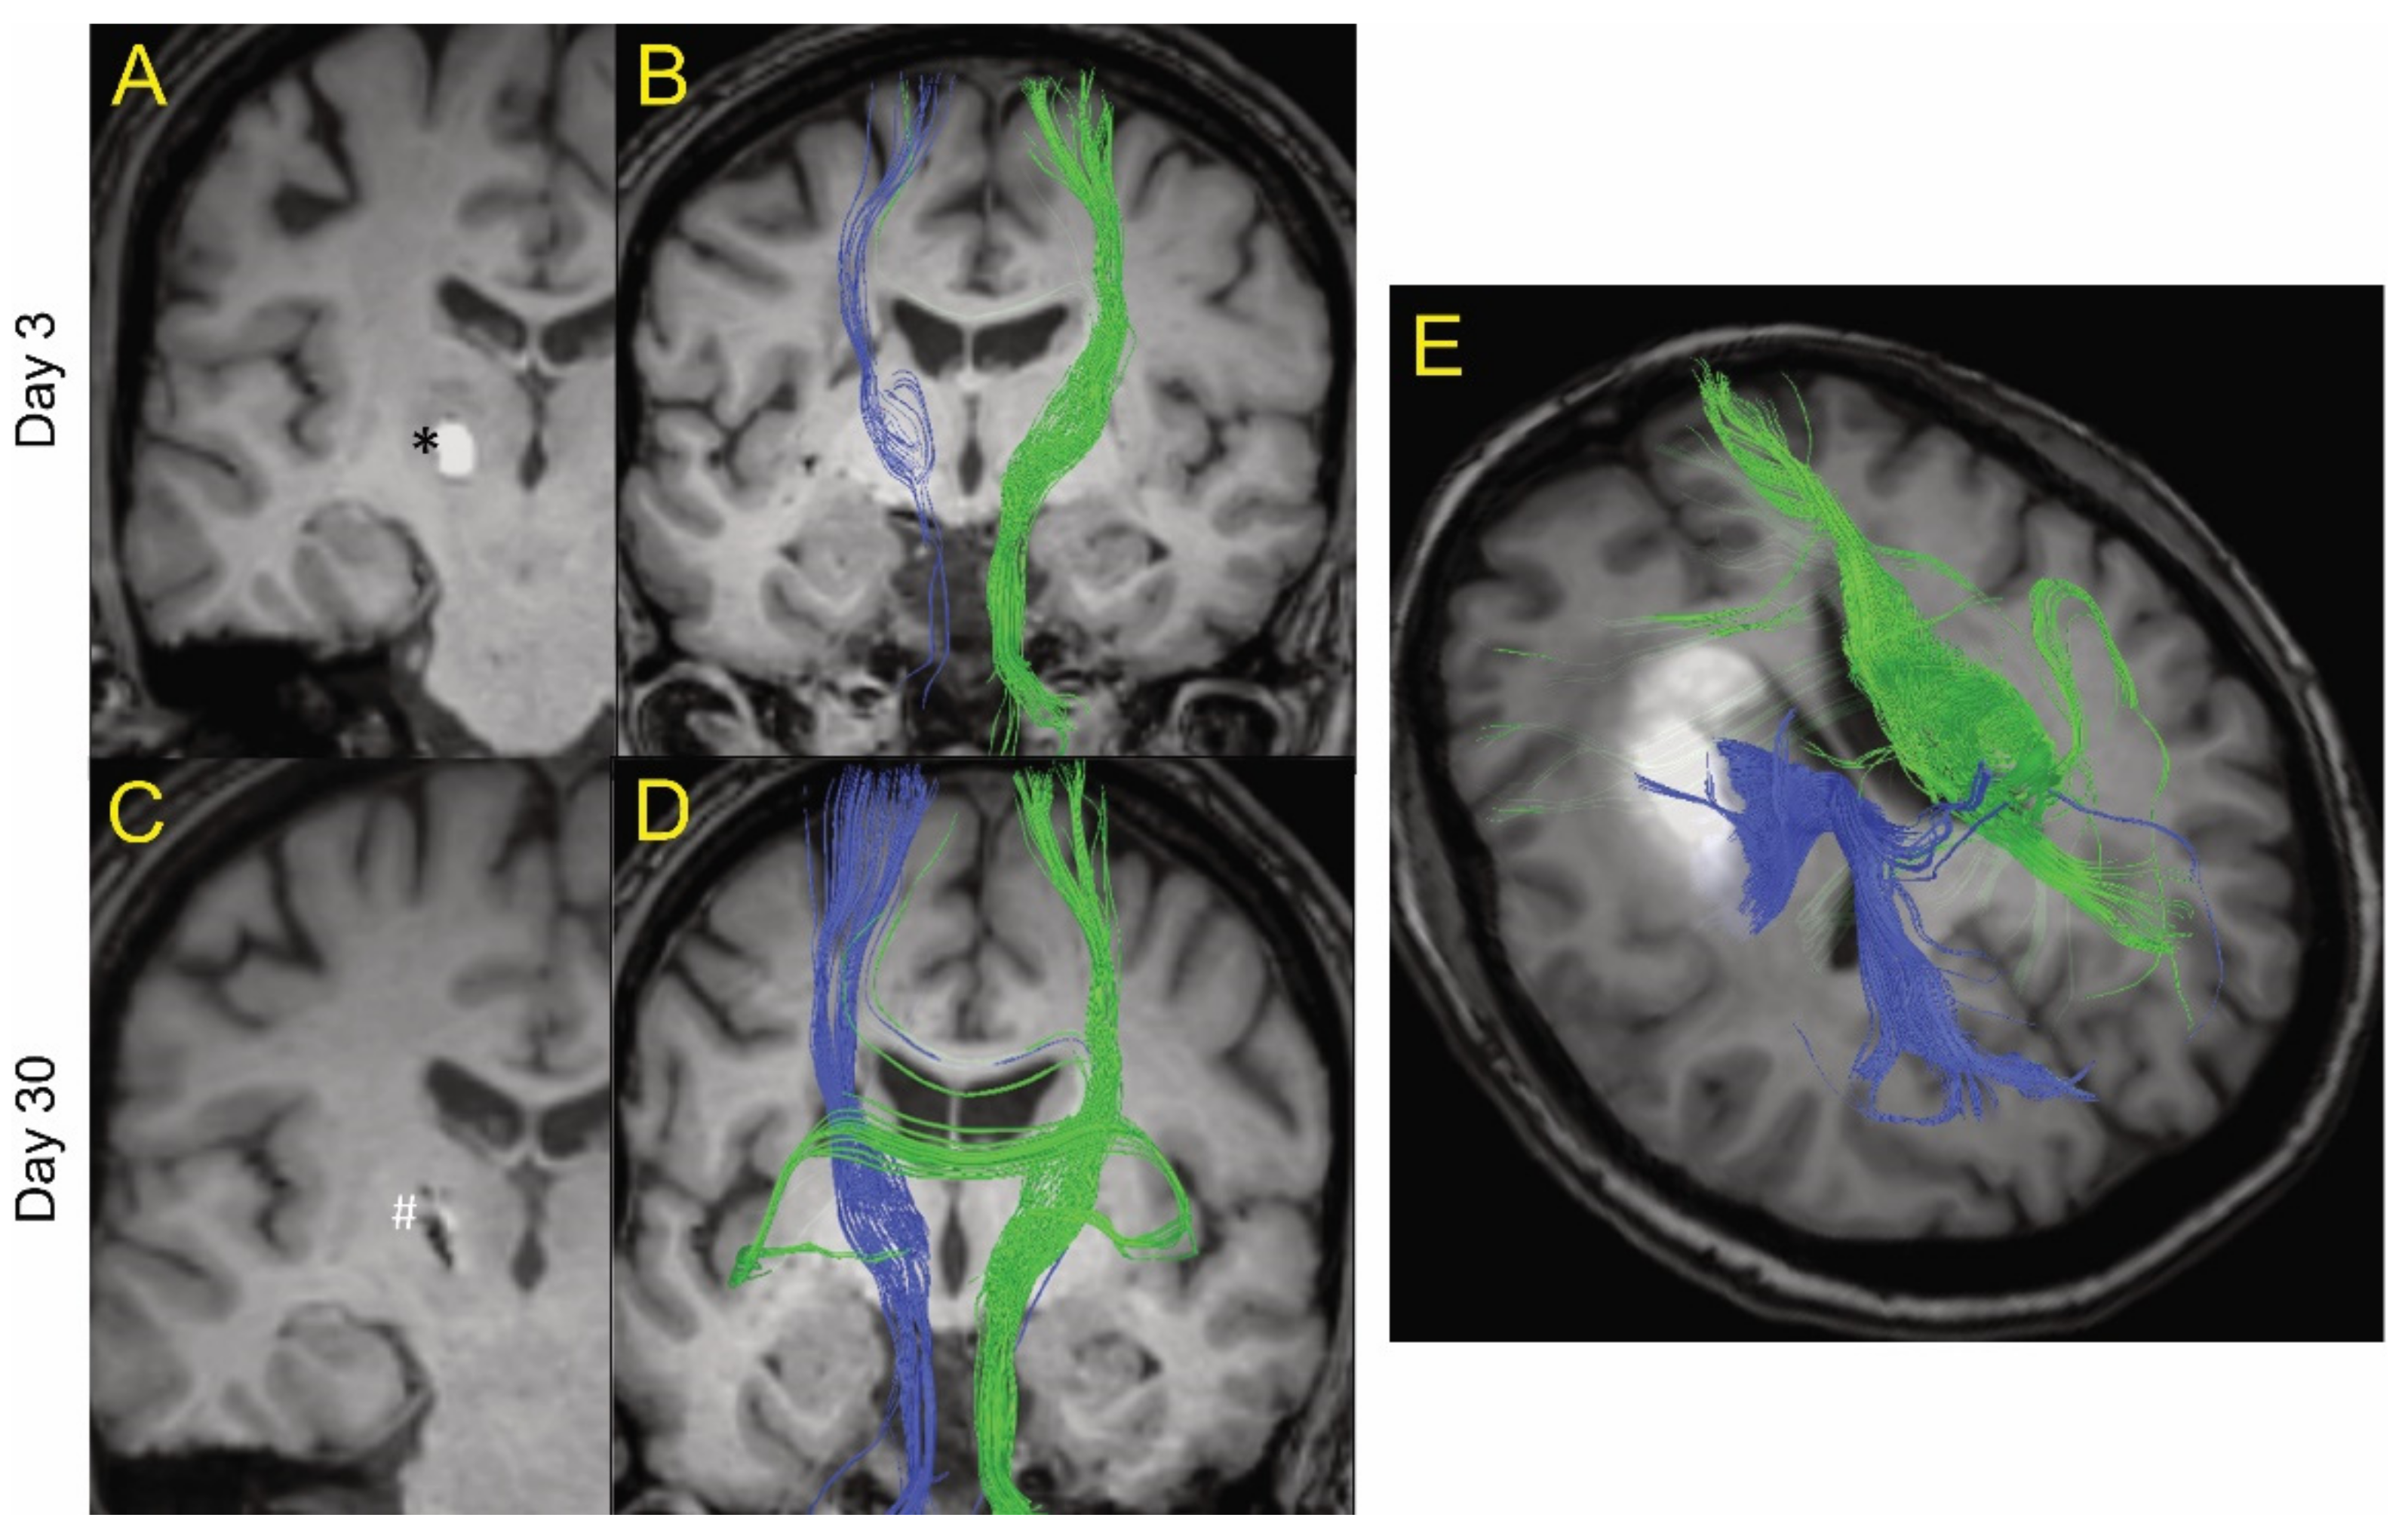

Images were analyzed using 3D Slicer software (available online: https://www.slicer.org/, accessed on 4 January 2021). DTI (FA, linear- and planar-anisotropy, ADC eigenvalues and trace, and b = 0, 800 diffusion-weighted imaging (DWI)) were created and stored in MetaImage (*.mhd, *.raw) format. In two patients (included in Figure 1), tractography was postprocessed on DTI images. The directionality of collective eigenvectors of the CST was assigned a color code (green), and the ipsilateral (blue) and contralateral (green) were differentiated for visual inspection. The integrity of the white matter was evaluated using FA maps. FA measurements were used indirectly to reflect changes to white matter, since it is heavily modulated by the degree of fiber unidirectionality, which varies with location in the brain. This bias was mitigated using 3D spherical segmentation volumes on FA maps to encompass the ICH lesion and the same anatomical location within the contralateral hemisphere. Voxels having an FA volume > 0.5 were used as a simplified index of directional white matter. Ill-defined voxels assigned values of non-assigned nominal (NaN) will, therefore, not interfere with data analysis. Normal and densely packed white matter fibers are completely isotropic or directional on DTI, having a value of 1. Other not so densely packed white matter fibers may display lower numbers of FA, like 0.7–0.9. To include disrupted fibers in the event of a hematoma, FA 0.5 was thought to be a good comprehensive threshold for calculations and would reflect the proportion of WM with relatively retained directionality. The bias was further mitigated by comparing ipsilateral volumes to their contralateral equivalents (difference in contralateral and ipsilateral volume > 0.5 FA). The radius of the spheres, drawn as areas of interest within the ICH and within the contralateral hemisphere, ranged between 2.0 and 2.5 cm. Sphere size was chosen with consideration to the lesion location, size, and surrounding structures, being careful not to cross the midline. Diameters of the spherical segmentation volumes were held constant for each subject to quantify evolution over time. The ipsilateral sphere was divided into lesional (the hematoma itself) and perilesional (defined as the surrounding tissue of the hematoma up to the edge of the sphere of interest) volumes, where lesional volume was defined by the boundaries of the lesion (hematoma) using DTI b = 0 labeled maps and then superimposing those labeled maps on the corresponding FA series map.

Figure 1 shows MRI tractography of two ICH patients. Figure 1A–D show the MRI tractography of a patient (age 50s) with a 0.3 mL hematoma at days 3 and 30 post ictus. At day 3, visually, there was evidence of a reduction in white matter tract fiber density ipsilateral to the hematoma compared to contralateral. Interestingly, some of the visualized ipsilateral WM tracts actually traverse the ICH. By day 30, there was near complete resolution of the hematoma and an apparent recovery of white matter tract fiber density ipsilateral to the lesion as grossly visualized. Figure 1E shows the MRI tractography of a patient (age 60s) with a larger hematoma (19.4 mL) at day 14. It too shows evidence of white matter tracts crossing the hematoma. These results led us to try to quantify the presence of organized white matter (here defined as FA > 0.5) both within the hematoma and around the lesion over time after ictus. The primary goal of the analysis was to analyze the percentage change between two time points for lesion and peri-lesion volume. The authors hypothesize that, in a larger sample of patients, it will be useful to analyze the above data adjusted for covariates like age, gender, and hematoma size; however, given the small sample in our study, this function was thought not to be scientifically meaningful.

Figure 1. Example of MRI tractography of intracerebral hemorrhage patients. The images are postprocessed 2D axial images with projected WM fibers in 3D in a cranio–caudal direction. One patient (age 50s) is shown at day 3 (A and B) and day 30 (C and D) after ictus. Blue fibers are ipsilateral and green fibers are contralateral to the hematoma. At day 3, there was a general decrease in the fiber tracts (blue) ipsilateral to the hematoma (shown as * in A) compared to contralateral tracts (green). However, there was evidence of some white matter fibers crossing the hematoma. At day 30, the hematoma has largely resolved (shown as # in C) and there was a recovery of the ipsilateral fiber tracts. (E) MRI tractography of a patient (age 60s) with a larger hematoma (19.4 mL) at day 14. It too showed evidence of white matter tracts crossing the hematoma.